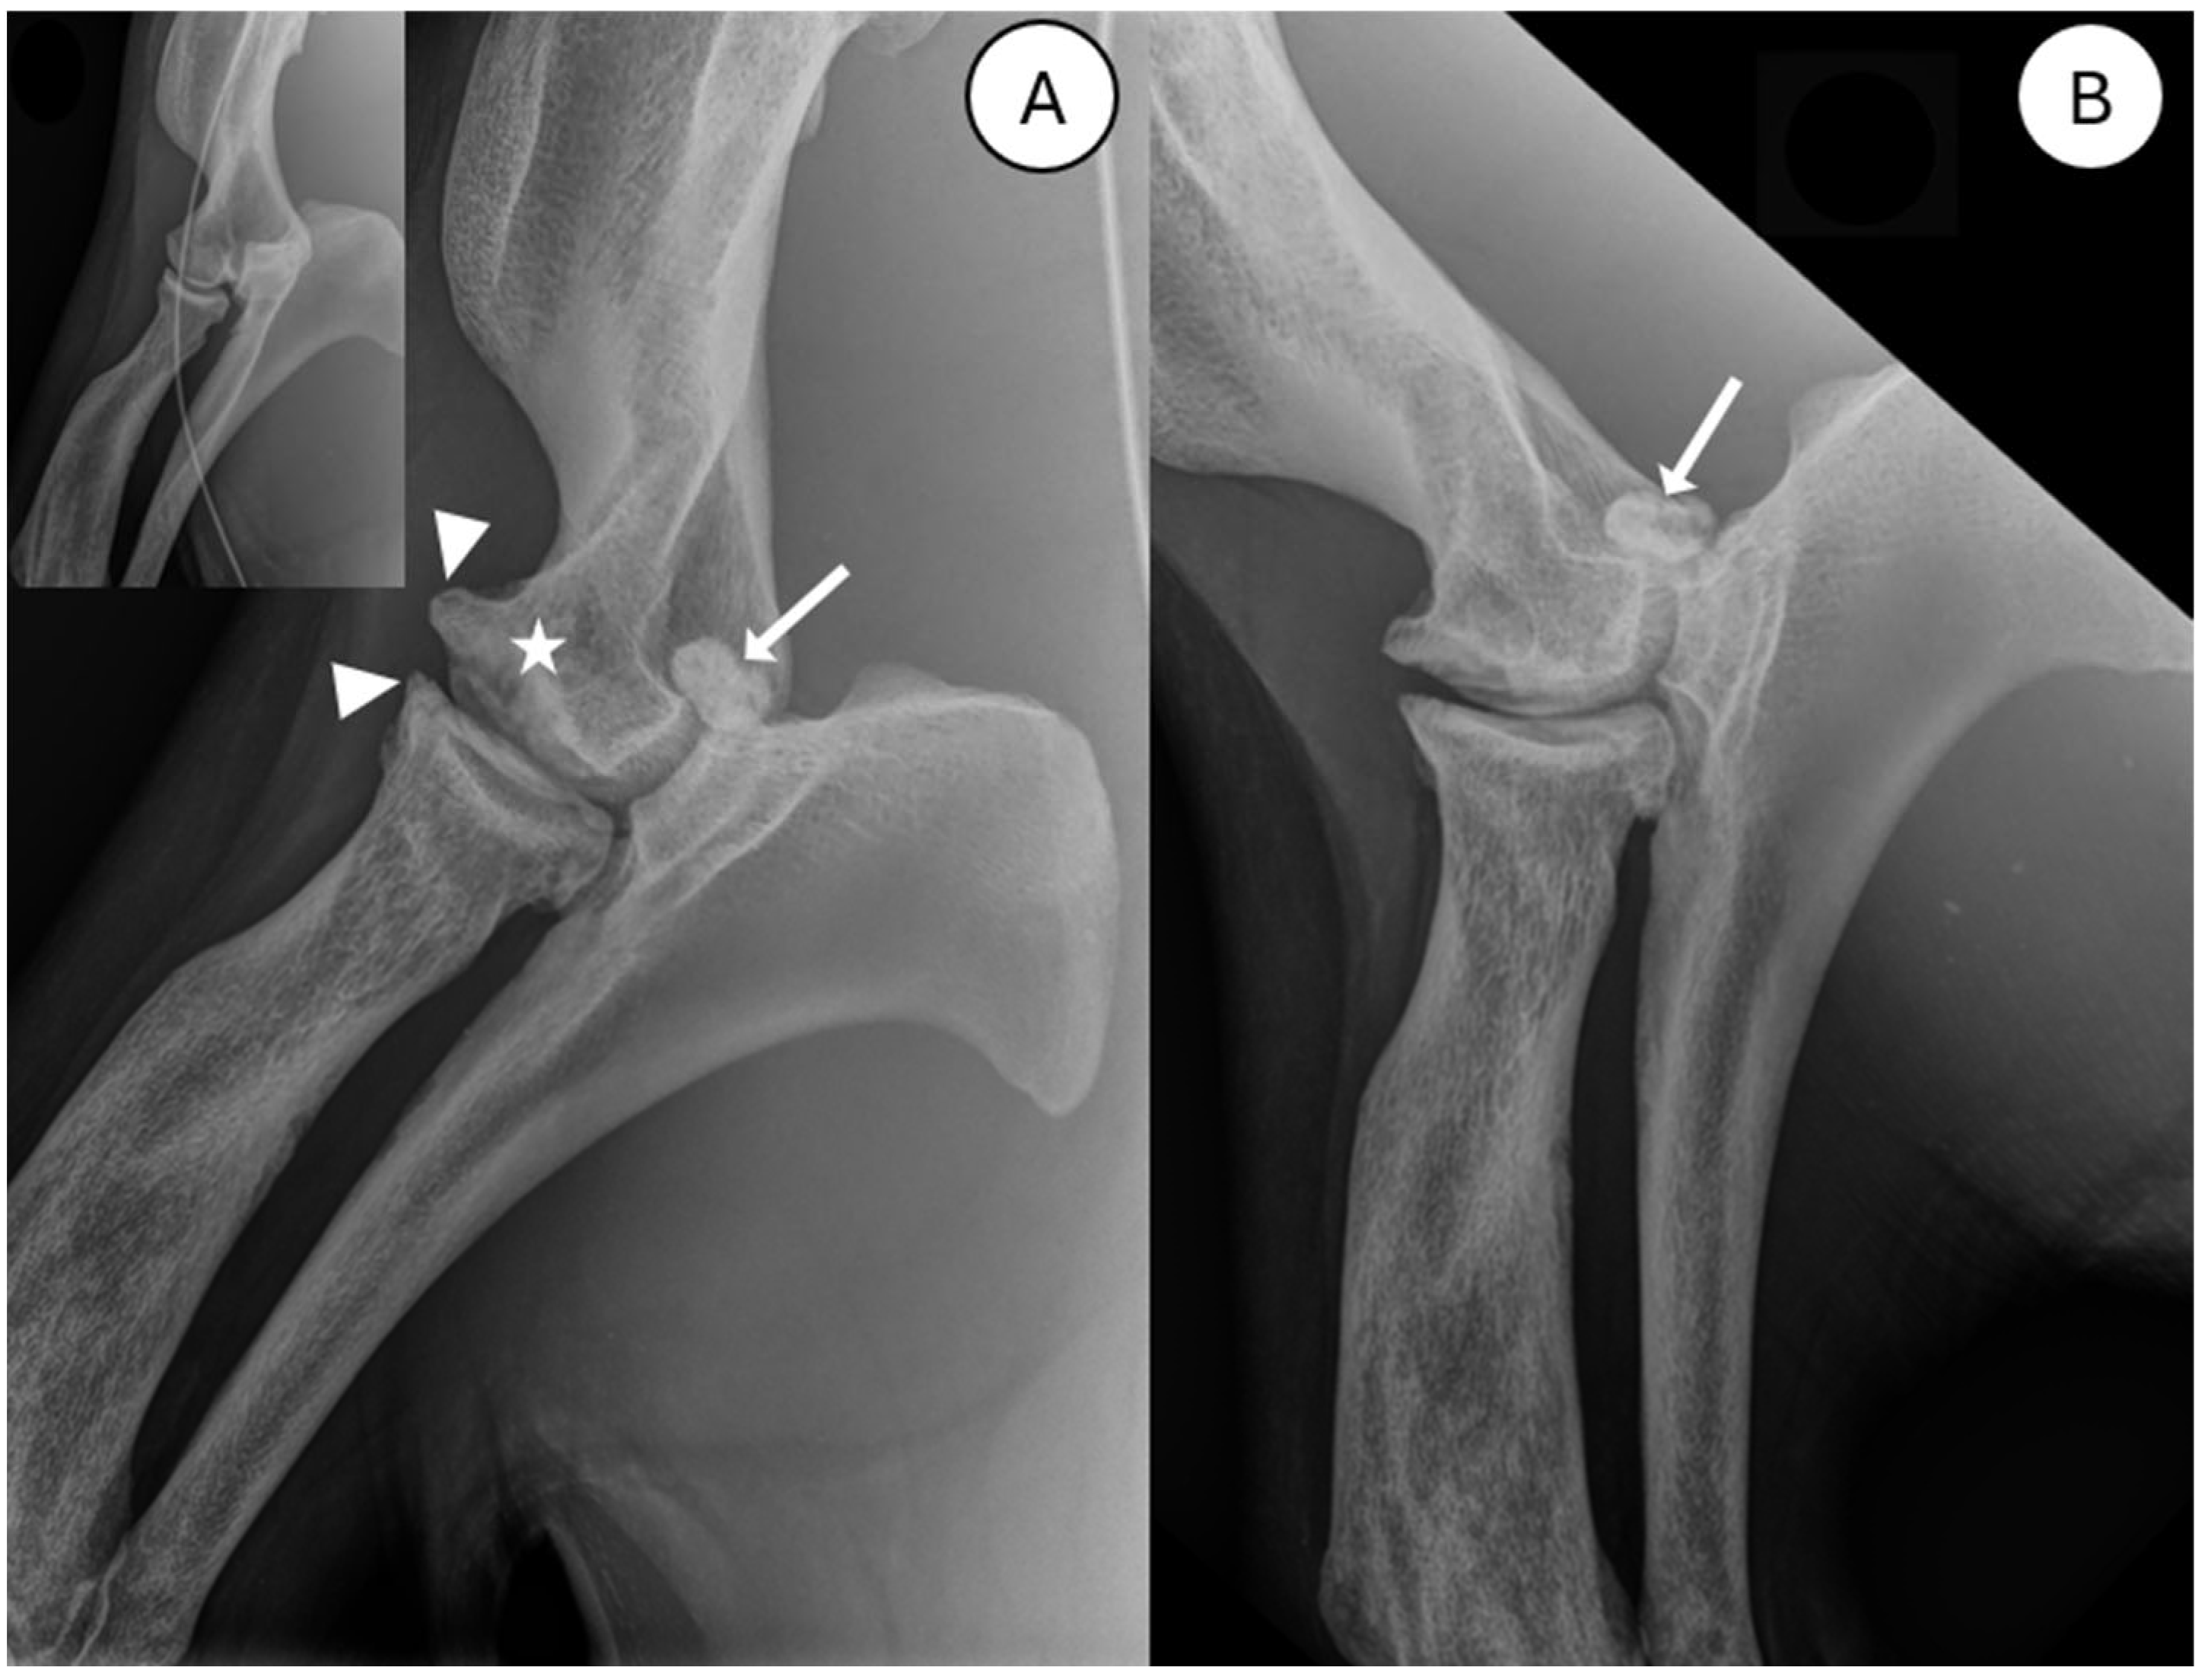

3.1. Radiography